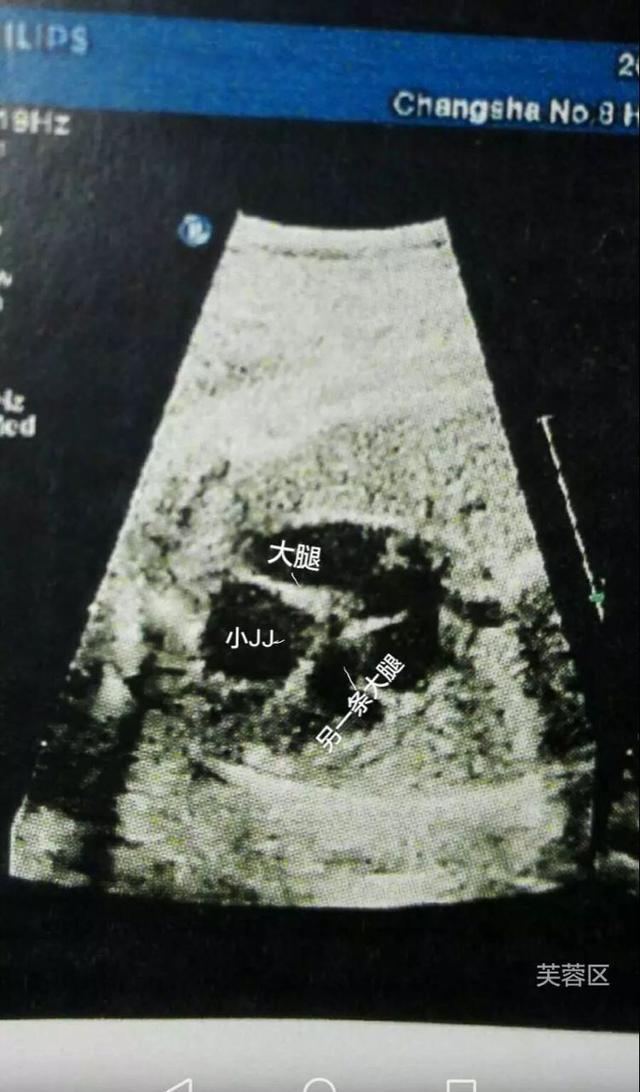

b超,确认是男宝一枚,现在和大家分享一下我怀

500x375 - 101KB - JPEG